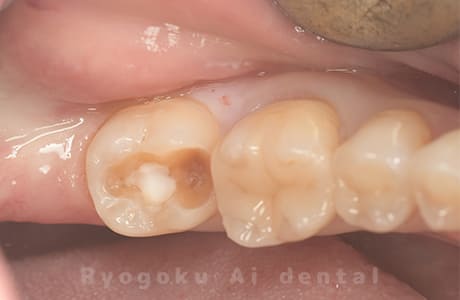

Case08

-

- 原因

- 虫歯

- 治療内容

- セラミックインレー

- 治療費用

- 77,000円

奥歯の黒い点が気になるということで来院された患者さんです。白い詰め物を外したところ、虫歯が中で大きく広がっていたため、患者さんと相談し、セラミックインレーで治療を行いました。